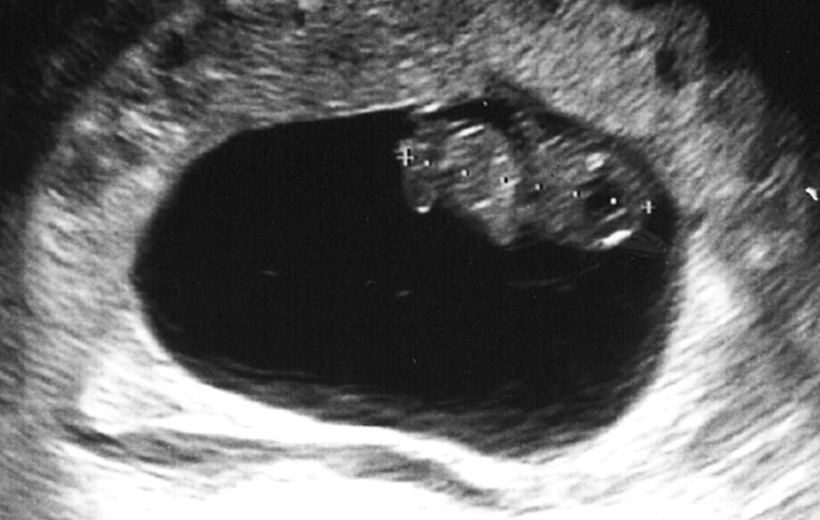

Na een positieve test werd het wachten op de eerste echo. Begin juni mochten we onze eerste opwachting maken voor een controle in het ziekenhuis met daarbij een echo. Hieronder de eerste foto’s. Nu lijk ik nog het meest op een rijstkorrel met een kloppend hartje.